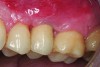

The implant of the patient shown in Figure 8 demonstrated all three of the red flag situations: it was placed too far buccally, had inadequate bone and soft tissue at the time of implant placement, and lost bone and soft tissue post implant placement. Correcting this required increased time, cost, and surgeries (Figure 9).

A implant restoration with a buccal dehiscence of bone and soft tissue caused by poor implant positioning, lack of keratinized tissue prior to implant placement, and soft tissue recession post implant restoration.

Figure 8

The same implant in Fig 8, 7 years following treatment, which included two autogenous connective tissue grafts and a bone augmentation surgery with a combined allograft and xenograft mixed with two biologics.

Figure 9